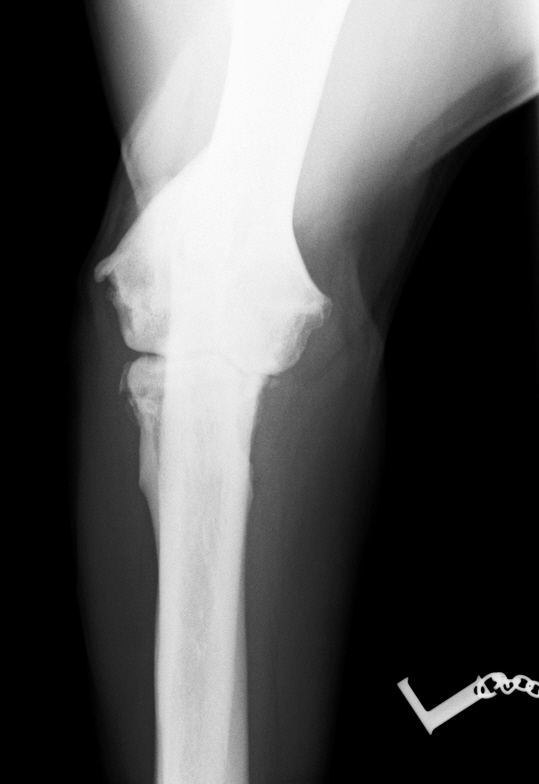

Im August 2013 wurde ein acht Jahre alter männlich kastrierter Labrador mit beidseitig hochgradiger  Ellenbogengelenksarthrose vorgestellt. Der Hund war beidseits wegen eines frakturierten Processus Coronoideus (Der Proccesus Coronoideus stellt einen wichtigen knöchernen Stabilisator des Ellenbogengelenks dar) operiert, einseitig nachoperiert und auf beiden Seiten mehrfach mit Cortison-Injektionen behandelt worden.

Noch im August 2013 wurde er in Vollnarkose beidseits mit der Thrombozytentherapie behandelt. Thrombozyten sind sogenannte Blutplättchen, die eine wichtige Rolle bei der Blutstillung spielen. Sie heften sich bei Verletzungen an das umliegende Gewebe an und sorgen dafür, dass u.a. geschädigtes Gewebe wieder "aktiviert" werden kann. Bei dieser Behandlungsmethode werden diese aus dem eigenen Blut des Hundes gewonnen und aufkonzentriert. Die Filtration mit V-Pet ist die Methode, um besonders viele und wirksame Thrombozyten schonend zu erhalten. Das Konzentrat wird anschließend in das geschädigte Gewebe gespritzt - in diesen Fall in das befallene Ellenbogengelenk des Labradors.